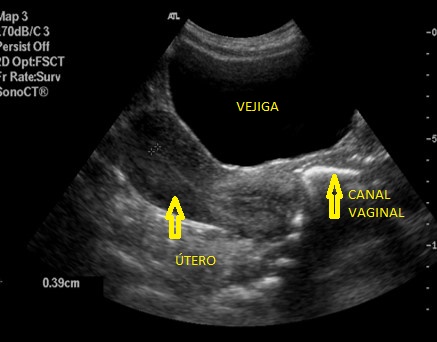

Saco de Douglas con líquido. Anecoico en profundidad al útero.

En ocasiones podemos ver el Fondo de saco de Douglas con líquido y eso debe ser valorado por el radiólogo/a.